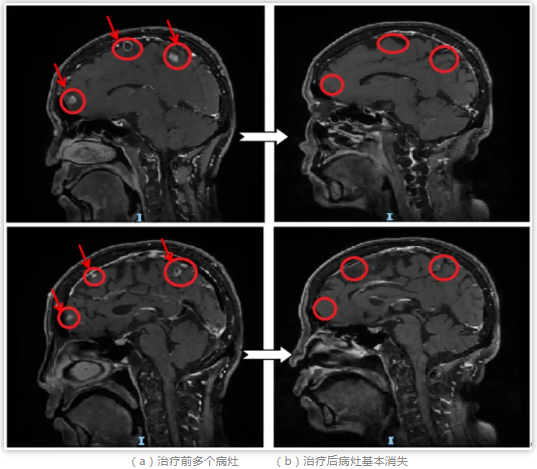

王女士最近很苦“脑”,发现肺部肿瘤复发转移到了脑部,新发病灶多达6颗。为提高放疗疗效、减少放射损伤,肿瘤科团队提出采用新近开展的 “多靶点精准放射治疗技术(MTPRT)”进行治疗。相较于全脑放疗而言,该技术不容易脱靶,能够更有效保护靶区外的正常脑组织,降低患者的副反应。

在肿瘤中心专家团队指导下,放疗医生、物理师、治疗师、护士等各专业人员紧密配合,王女士经历了“患者定位—大孔径CT下模拟定位—多靶点肿瘤计划设计—治疗前的计划验证和位置验证—适时治疗”的放疗流程,目前已经顺利完成了一个疗程的放射治疗,其间无明显不适,脑部的转移瘤也基本消失。